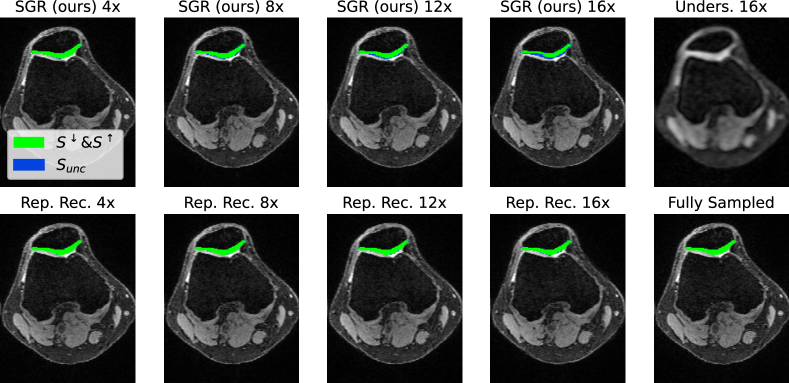

Figure 4: Analysis of different acceleration factors. For RR, we see that the uncertainty does not increase, even though very high accelerations are tested. Our method, in contrast, generates more reliable uncertainty boundaries.

In Fig. 4, we see that the uncertainty boundary increases with higher acceleration for our method, while it stays approximately constant for the baseline method RR. This result is also shown in Fig. 5, where the ratio Vunc/Vsegsubscript𝑉𝑢𝑛𝑐superscriptsubscript𝑉𝑠𝑒𝑔V_{unc}/V_{seg}^{\uparrow} increases faster for SGR compared to RR. Given the relatively low precision and recall scores for RR and the higher scores for our method, one can conclude that RR underestimates the uncertainty boundaries, while this problem is largely reduced for the uncertainty boundaries estimated by SGR.